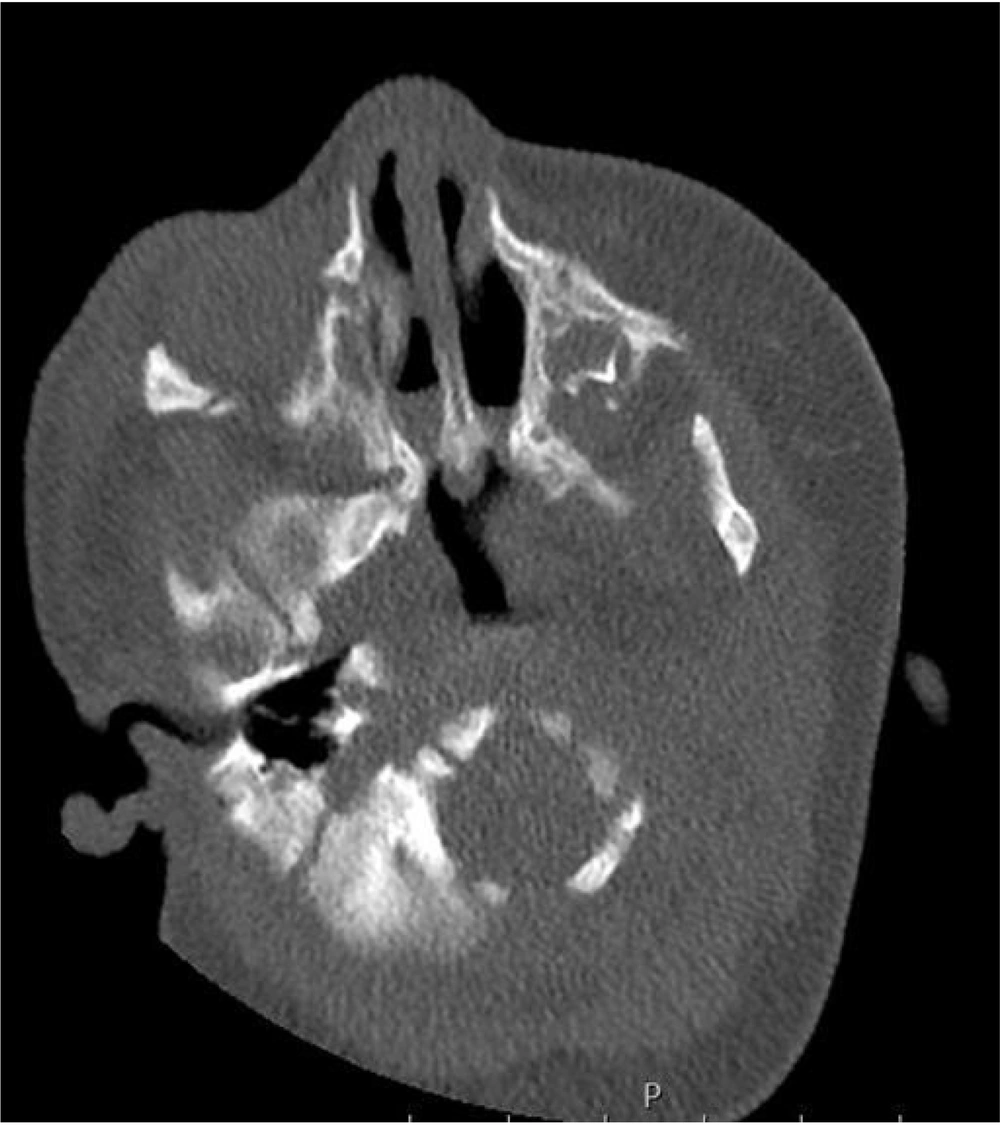

Non-contrast CT of the nasal cavity and nasopharynx was evaluated in all patients by taking 2 mm thick contiguous sections in the axial plane parallel to the hard palate. Before the examination, nasal passage aspiration and intranasal decongestant were applied to all patients to prevent errors caused by nasal secretions. To reduce motion artifacts, patients were either examined during sleep or administered intranasal midazolam (Dormicum) 0.2 mg/kg. In all patients, the examination was performed without contrast. The CT images were evaluated for the presence of choanal atresia, whether bilateral or unilateral type (bone, membranous, mixed), and middle nasal cavity stenosis (Figure 1). Craniofacial anomalies, if any, were also recorded on cranial CT. The medical information for accompanying syndromes was also reviewed (9).